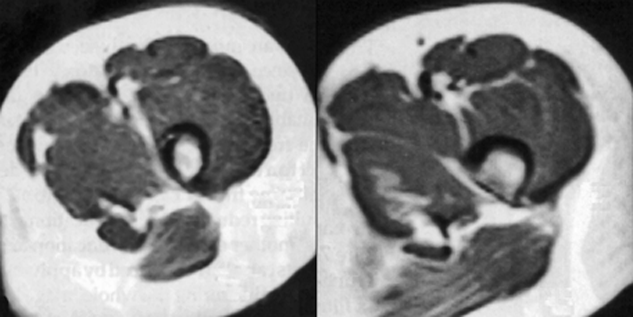

Figure 17-11:

High field strength (1.5 T) MR images with chemical shift artifacts in the read­out di­rec­tion, which is ori­­ent­ed vertically in the ima­ge. The chemical-shift arti­fact is vi­si­ble as a black rim between fat and muscle.

Since this is a frequency-dependent artifact, the effect will be more pro­noun­c­ed at high and ultrahigh fields (1.5 T, 3.0 T, and more), with displacements of several pi­xels being visible in the readout direction. The artifact can be reduced by using stron­ger gra­dients, but this has the unfortunate side effect of decreasing the sig­nal-to-noise ratio.